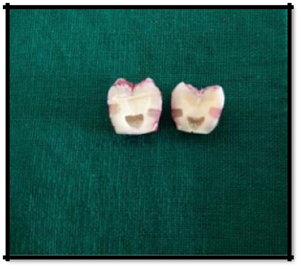

Standardized class V cavity preparations were made on the facial and lingual surfaces of each tooth, with no 245 straight fissure bur (Mani, India) in a high speed hand piece (NSK Pana Air, Japan) utilizing water-spray coolant. Standardized preparations were obtained by making cavity preparations approximately 2mm wide, 2mm deep and 3mm long, paralleling the cemento-enamel junction (CEJ). The depth of the preparations was assessed using a periodontal probe (GDC, India). The gingival halves of the preparation were extended 1mm below the CEJ (Figure 2). Prepared surfaces were rinsed with distilled water for 20seconds followed by air drying for 20seconds a two-way syringe. The teeth were then randomly divided into two groups:

Figure 2 Standardized class V cavity preparations were made on the facial and lingual surfaces of each tooth.